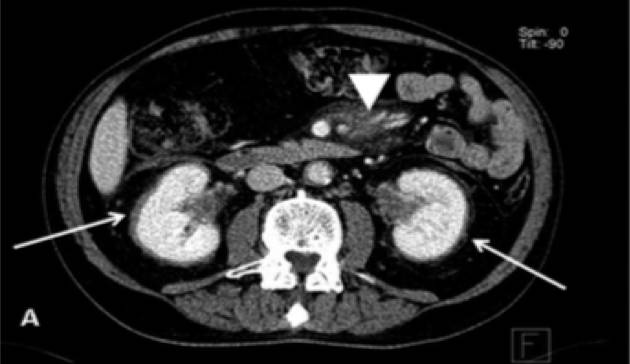

整体观察见MIP图(图3)。主要阳性发现包括:左心房、主动脉及肺动脉主干周围可见环形、弥漫性FDG摄取(SUVmax 3.8),但相应部位平扫CT未见明确异常结构改变(图4);右肾盂扩张,内见形态不规整FDG摄取增高软组织密度肿物影(SUVmax 4.9),边缘毛糙,范围约3.6 cm×2.9 cm×3.0 cm,并包绕上段输尿管,同时见右肾盂积水(图5);四肢长骨FDG摄取对称性增高(SUVmax 3.2),自关节端向骨干伸,相应部位CT见不规则骨质硬化,其中右股骨内侧髁可见溶骨性骨质破坏(图6);脊柱及骨盆亦可见多发性质类似的骨病变(图7、8)。

腹膜后及肾脏受累者约占68%,以肾脏受累多见。组织细胞可浸润肾窦、肾蒂、肾周脂肪间隙及输尿管等部位,导致肾脏实质受压、尿路梗阻,引起肾功能损伤。影像学常见肾周软组织浸润的“毛发肾”(图13)。

![]()

图13. 毛发肾